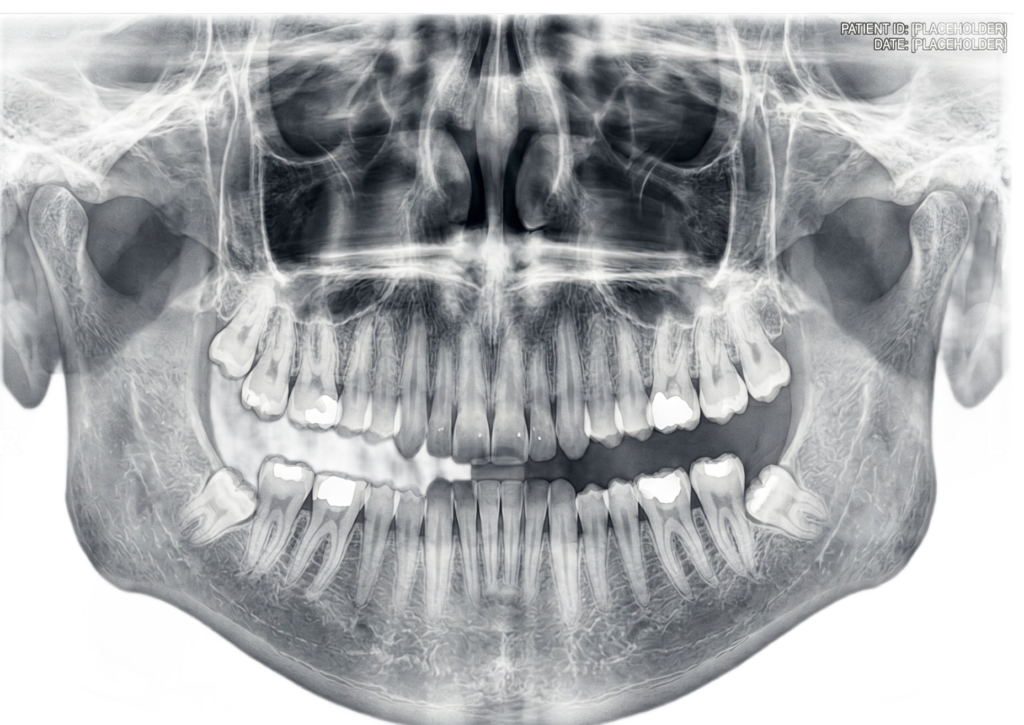

Advanced CBCT & Dental Imaging Services provide precise, high-resolution 3D scans for accurate diagnosis and treatment planning. Using modern technology, we ensure fast, reliable results with minimal radiation exposure. Our expert team focuses on patient comfort, delivering safe, efficient imaging solutions to support dentists in achieving better clinical outcomes.

He is certified in Cone Beam Computed Tomography (CBCT) and has extensive experience in advanced radiological diagnosis. Dr. Singh is associated with several reputed centers across India as a consultant radiologist for CBCT reporting. His expertise includes implant planning, impacted teeth localization, oral and maxillofacial pathology interpretation, TMJ assessment, maxillary sinus evaluation, and airway analysis.

OPG 600–800/-